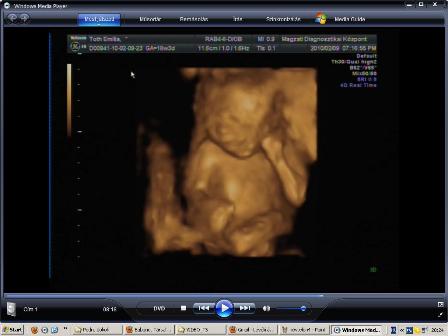

Leszedtem, a dvd-ről a fütyi+zacsi bizonyítékunkat, hogy megmutizzam :D:D:D:D

Igaz csak 2D, de jól látszik a fütyi és a zacsi is 16+6 hetesen :)